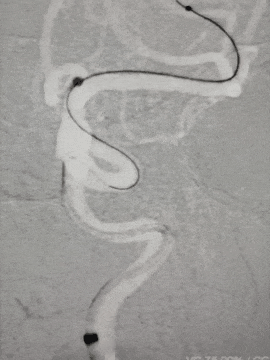

右侧颈内动脉:

Synchro 2导丝和XT-27同轴带CAT5到大脑中M1段远端

路径迂曲,海绵窦III型导致基础支撑不足,长鞘下坠,Surpass Streamline血流导向密网支架无法到位。

Infinity长鞘轻松推送至海绵窦段高到位,微导丝和CAT 5送高,增强系统支撑,支架顺利到位。